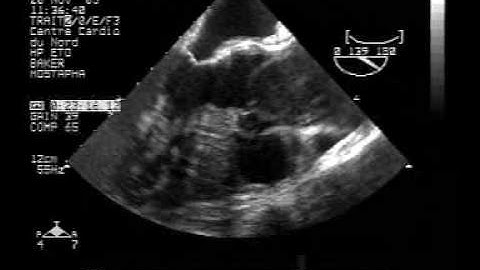

echocardiogram tee:localized dissection 1/3of the ascending aorta